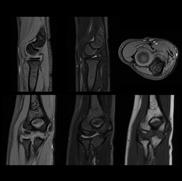

PD STIR - 1024 x 1024 matrix - 3mm slice thickness

Sag T2 - 0.5 x 0.5 min - 0:56 min Ax PD FatSat - 0.6 x 0.6 mm - 1:30 min Cor PD FatSat - 0.6 x 0.6 mm - 1:15 min Cor PD - 0.5 x 0.5 mm - 0:58 min © 2020 CANON MEDICAL SYSTEMS // MREU200040

Fast knee protocol with AiCE on Vantage Orian 1.5T